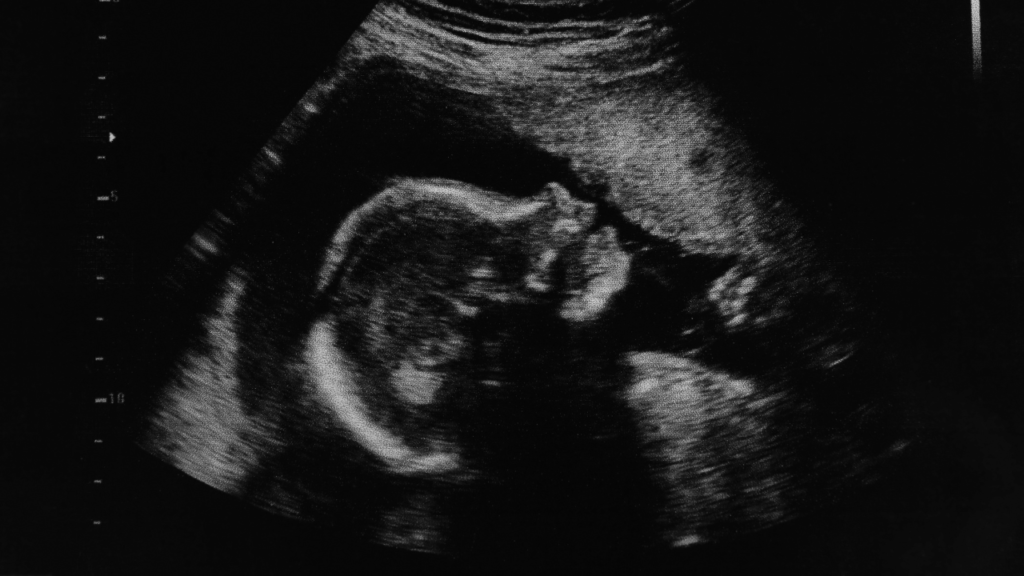

If it proceeds unamended, Clause 191 will decriminalise abortion up to birth: this means that any women who perform their own late abortion after the legal limit of 24 weeks would no longer be considered to have committed an offence, irrespective of their reason. At this stage the baby is practising breathing and could survive outside the womb.